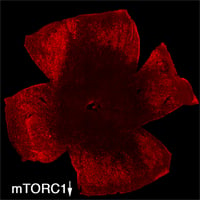

| Retinal Flat mount showing surviving cones in red at 2 months of age. Right image shows effect of loss of mTORC1 (fewer surviving cones at 2 months of age). Role over image to see the effect of increased mTORC1 activity on cone survival at 2 months of age. | |

To evaluate the long-term therapeutic potential of the insulin/mTOR pathway on cone survival, and test if insulin acted directly on cones through this pathway, we have now constitutively activated this pathway in cones through use of mouse genetics in two mouse models of Retinitis Pigmentosa. This has led to a robust and unprecedented cone survival effect in two mouse models of Retinitis Pigmentosa and to the finding that cone survival is driven solely by increased mTOR complex 1 activity (rollover image; Venkatesh et al., 2015). To study why the initial robust survival effect of constitutively activated mTORC1 does not persist indefinitely we further study the consequences of altered mTORC1 activity (Venkatesh et. al., 2016). Our studies show that it is not the strength of survival is directly dependent of the strength of mTORC1 activation but that the duration of the effect depends on the system's ability to intermittently turn of mTORC1. This knowledge will allow us to identify downstream genes of mTORC1 that mimic the positive effect of increased mTORC1 activity, without altering the systems ability to intermittently turn of mTORC1. In summary, the knowledge gained from these two studies will allow us to identify downstream target genes or pathways that when manipulated should extend vision in affected individual (see Jean Bennett commenting). For example, rAAV mediated gene transfer of mTORC1 targets in cones may provide a feasible approach for future treatments in humans. Alternatively, drugs that increase mTORC1 activity could be delivered to the retina through slow releasing eye implants. The focus of our current research is to identify the correct mTORC1 targets that can be used to prolong vision in humans with Retinitis Pigmentosa.